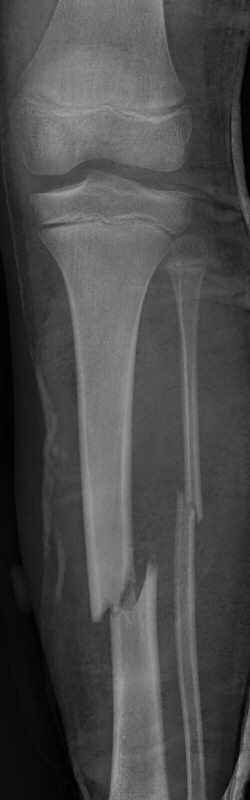

Tibiafraktur hos 7-åring, behandlades med gipsstövel

|